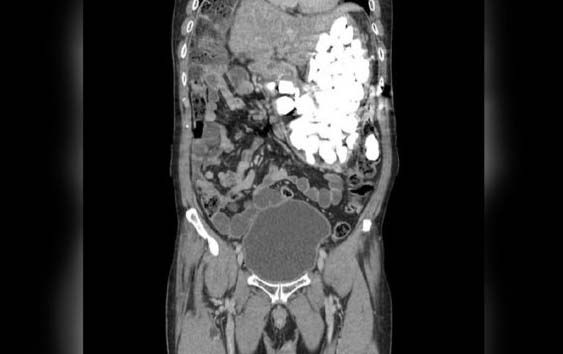

El cirujano Pyong Wha Choi dijo a la revista Journal of Medical Case Reports, que el paciente llegó a mediados de enero hasta la sala de emergencia del centro médico, y, tras realizarle una radiografía se detectó el material en el estómago.

El hombre reconoció que los estuvo ingiriendo durante la última semana por sus ataques de ansiedad.